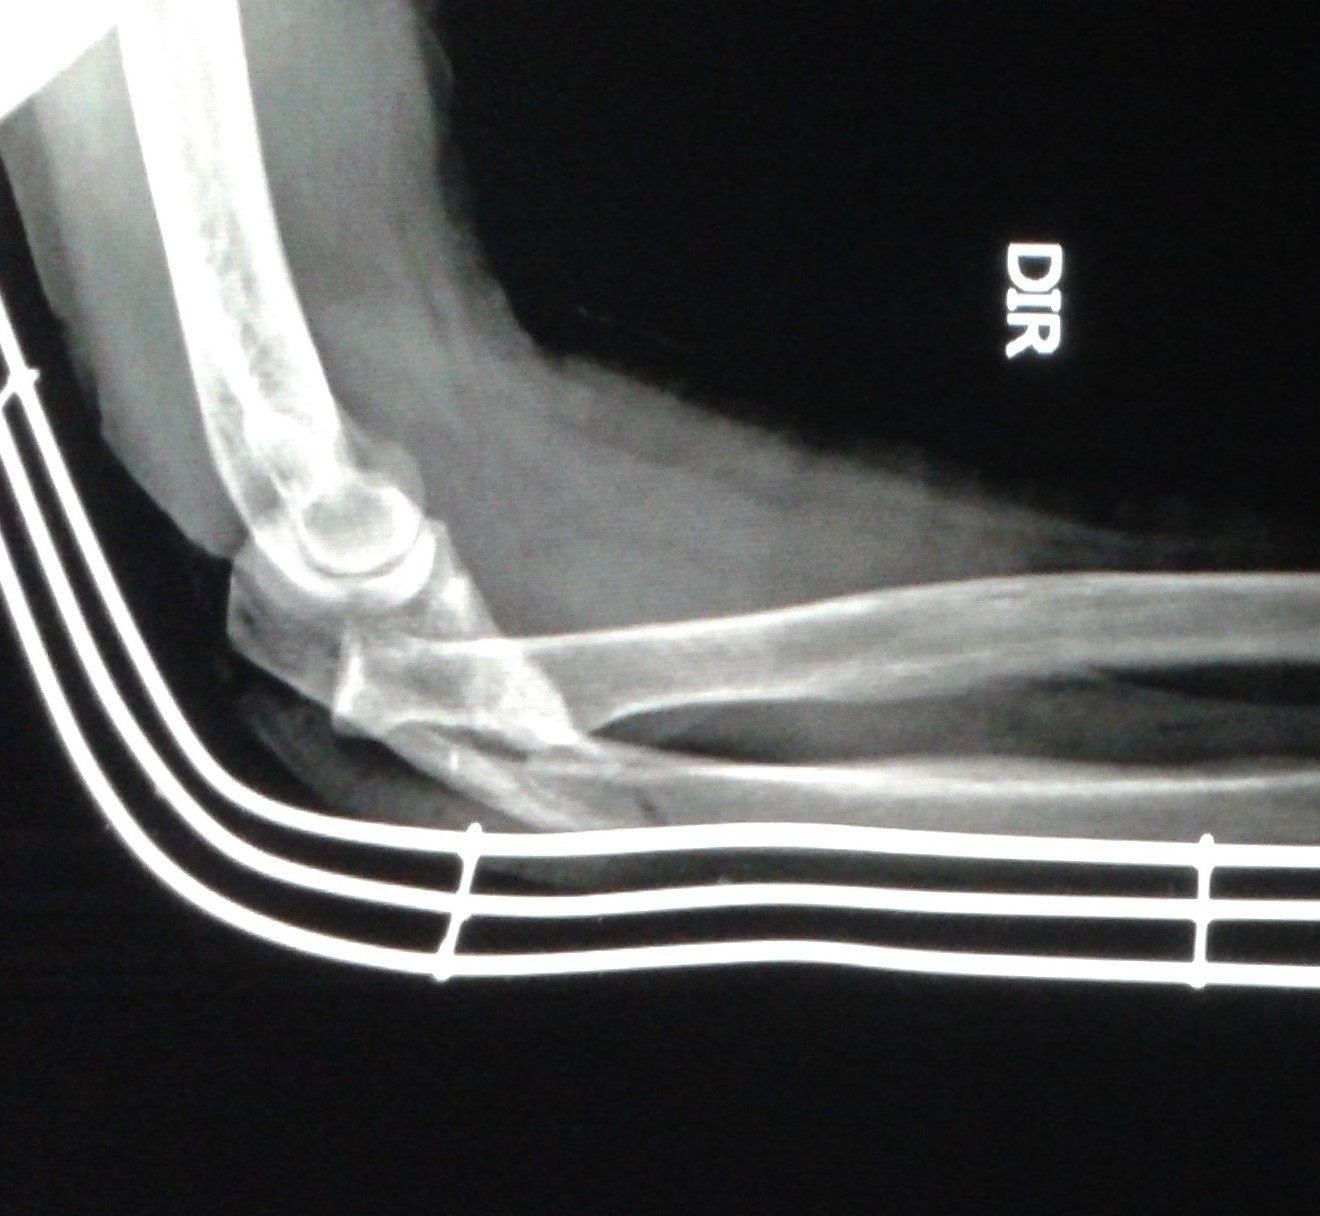

DICAS DE RADIOLOGIA Tudo Sobre Radiologia IMAGENS RADIOLÓGICAS FRATURA ULNA COTOVELO